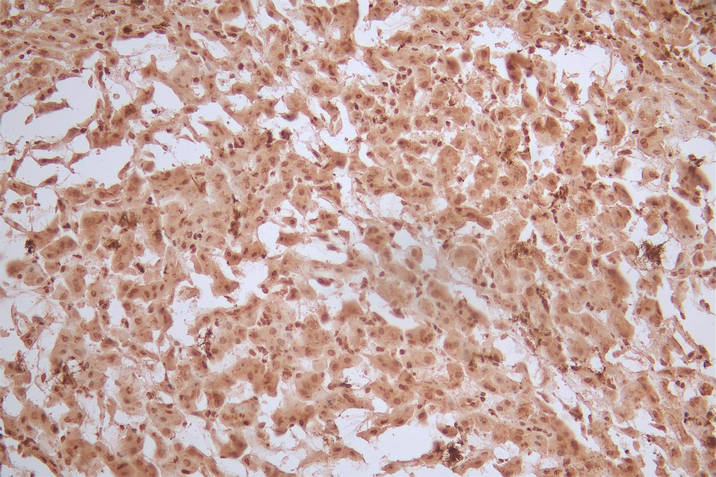

IHC image of CSB-RA009030MA1HU diluted at 1:50 and staining in paraffin-embedded human rectal cancer performed on a Leica BondTM system. After dewaxing and hydration, antigen retrieval was mediated by high pressure in a citrate buffer (pH 6.0). Section was blocked with 10% normal goat serum 30min at RT. Then primary antibody (1% BSA) was incubated at 4°C overnight. The primary is detected by a Goat anti-Mouse IgG labeled by HRP and visualized using 0.05% DAB.